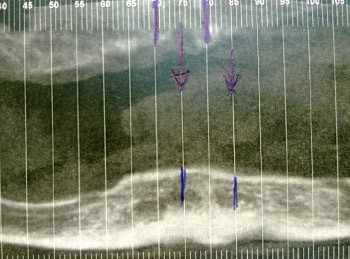

La littérature relève 12 cas d’hémorragies sévères à la suite d’interventions d’implantologie dentaire avec pour conséquences une obstruction des voies aériennes supérieures [4]. Ces hémorragies sont présentées comme la conséquence d’une perforation de la corticale linguale mandibulaire pendant la préparation du site implantaire, ou la déchirure du périoste lingual avec lésion extra-osseuse de l’artère sublinguale, ou enfin, quand aucune de ces deux précédentes circonstances ne peut être incriminée, la lésion des petits troncs artériels ectopiques non repérés, car non visualisés sur les examens radiographiques ou les scanners préopératoires.